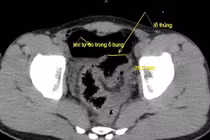

Bệnh nhân 66 tuổi được phẫu thuật thành công lấy tăm tre nhọn gây thủng đại tràng, cảnh báo nguy hiểm của thói quen ngậm tăm hàng ngày.